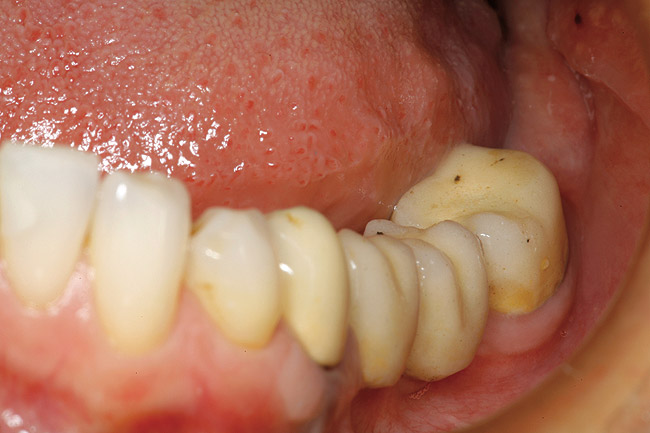

Figure 20  Buccal view of tooth No. 21, 8 weeks after resective surgery and master impression taking. A connective-tissue graft was also placed on the facial aspect to increase the amount of attached tissue. The post and core was cemented to place, but the provisional restoration would remain in place until the graft healed sufficiently, in case the periodontal specialist wanted to add more connective tissue.

Figure 20